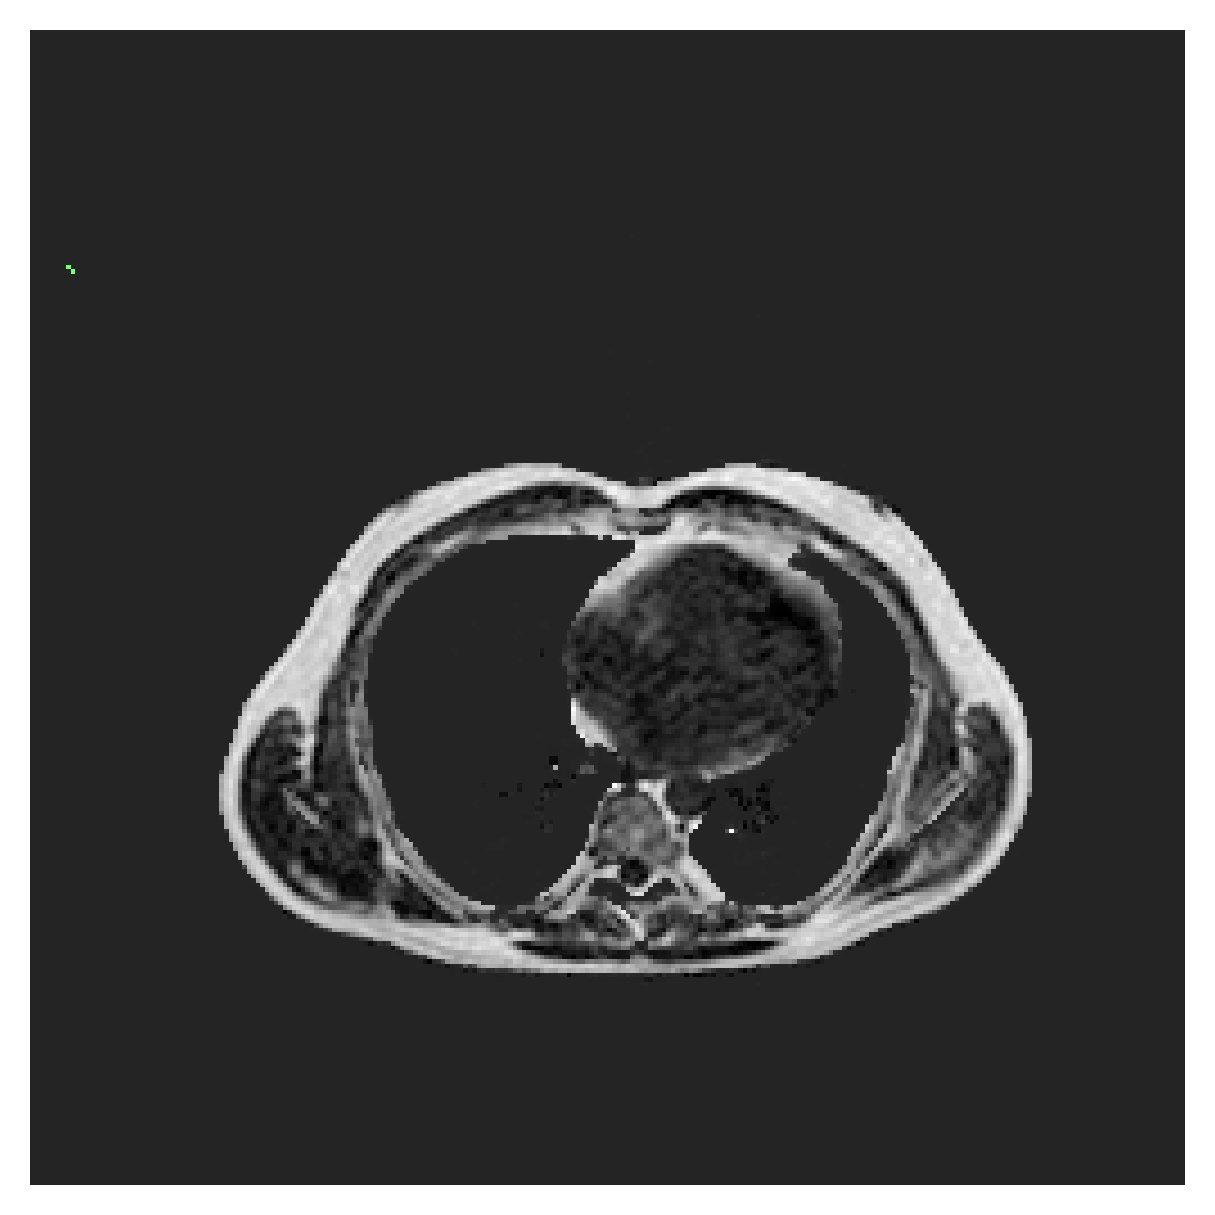

POEM

The Prospective investigation of Obesity, ENergy production and Metabolism (POEM) is a local (not currently publicly available; PI: L. Lind, see [22] for details) cohort of whole-body fat/water separated MR images. Full annotations of the liver, kidneys, bladder, pancreas and spleen are available for 50 subjects, providing a challenging segmentation dataset with heavily imbalanced classes of varying shapes. The resolution of the data is anisotropic, with reconstructed voxel size of in left-right, anterior-posterior and foot-head directions, respectively. For additional technical details regarding the acquisition and specifications of the images see [22].

The images contain two channels, one for water and one for fat content. For training, we normalize the volumes (per channel) and use 2D slices in the coronal plane, sized . The weak annotations are created synthetically, following the same procedure as described for the ACDC dataset.